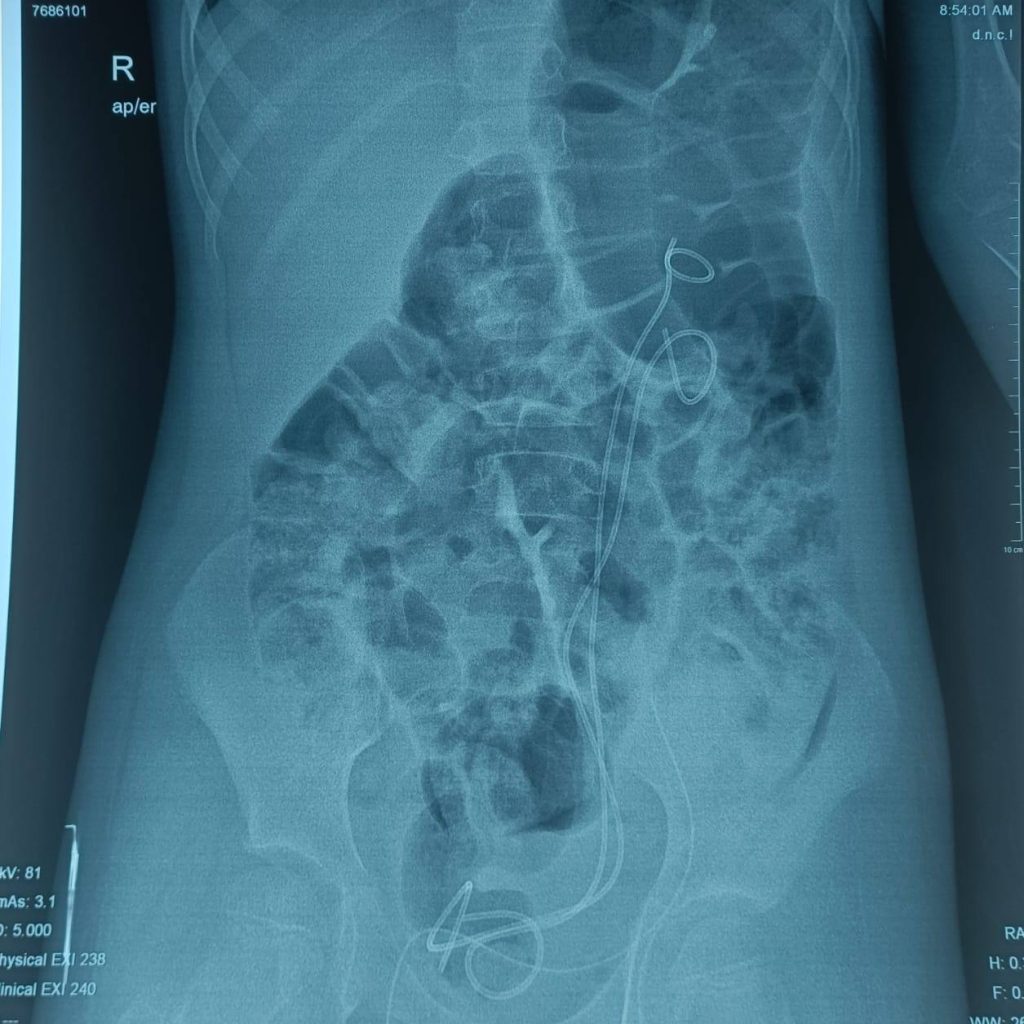

وأوضح الأعرجي أن الفحوصات السريرية والشعاعية كشفت عن تشوه خلقي نادر، مضيفًا:

“بيّن التقييم الطبي أن الكلية اليسرى كانت مقسومة إلى غرفتين منفصلتين، ولكل غرفة حالب مستقل يفتح في المثانة بفتحتين مختلفتين، وهي حالة غير شائعة وتخالف الكثير من الأنماط المسجلة في الأدبيات الطبية.”

وأشار إلى أن سبب المضاعفات كان خللًا وظيفيًا في الحالبين، موضحًا:

“كان الحالب العلوي يتسبب بارتداد البول من المثانة إلى الكلية، في حين كان الحالب السفلي يعاني من انسداد جزئي، ما أدى إلى استمرار الالتهابات والتوسع الكلوي.”

“خضعت الطفلة لعملية جراحية دقيقة استغرقت نحو ثلاث ساعات، تم خلالها إعادة زراعة الحالبين في المثانة بنجاح، مع الحفاظ الكامل على الغرف الكلوية دون أي مساس بوظيفتها.”